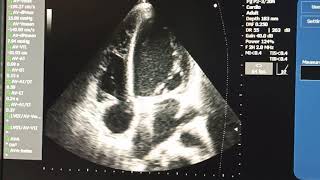

Ультразвуковая диагностика с Натальей Карауловой Замена аортального клапана аллографтом © Replacement of the aortic valve allografts

M E Д Ф И Л Ь М ЭхоКГ в оценке функции протезированных клапанов сердца и диагностике осложнений протезирования

Вебинар SonoScape и РАСУДМ. Лектор: Рыбакова Марина Константиновна, доктор медицинских наук, профессор кафедры ультразвуковой ...